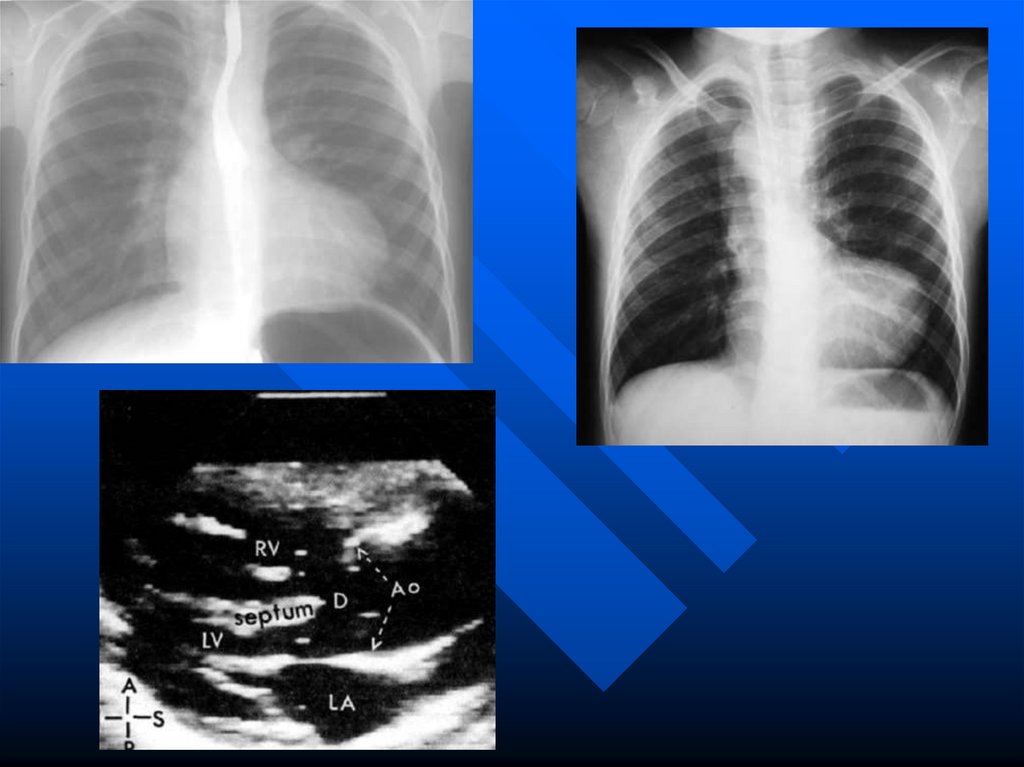

перегородок

формируется